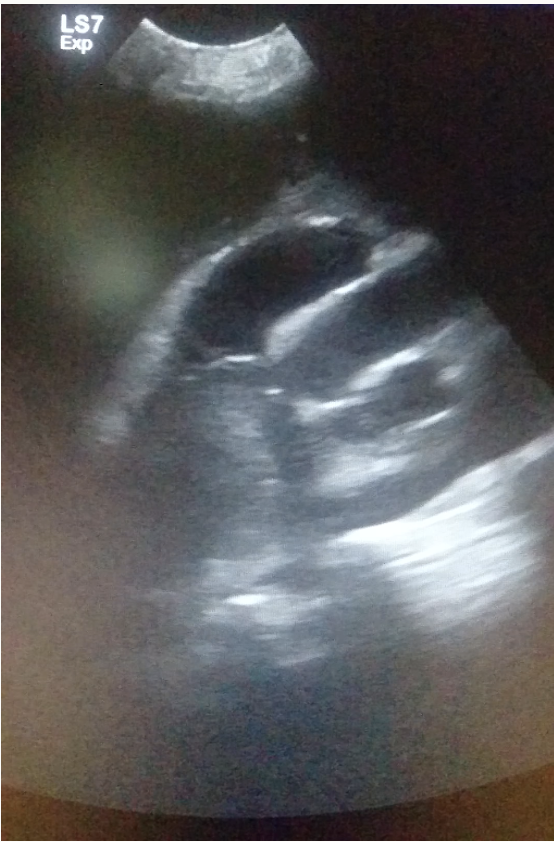

20

Q

What can you see in this lung ultrasound?

A

Pleural effusion